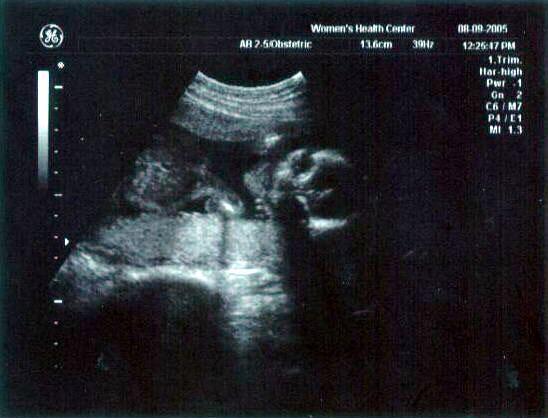

13 week ultrasound ~ The little one's getting bigger!